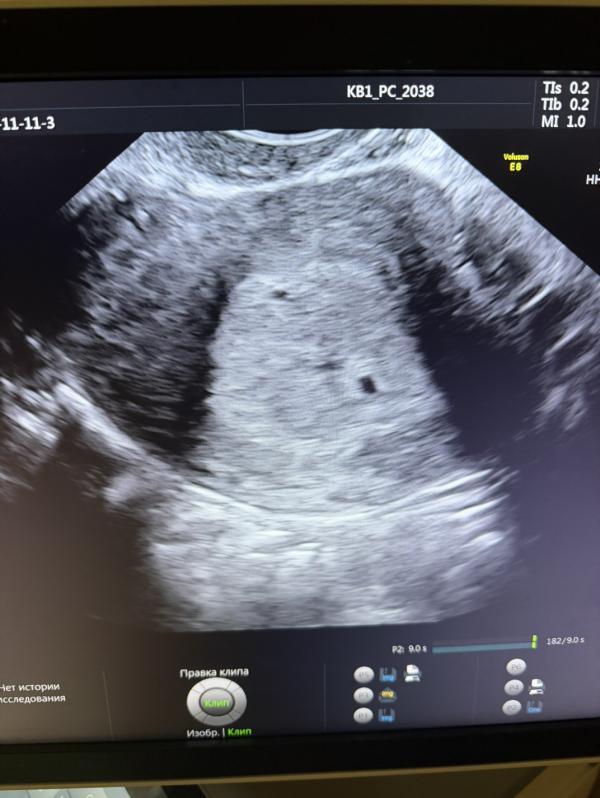

Сходила я на узи. Поставила маточную под вопросом, сказала что очень похоже на беременность, но после внематочной она не уверена

Что думаете? Точка, которая вверху матки 2,2мм

Также в 3-4 недели пя было 3 мм и тоже ставили ?